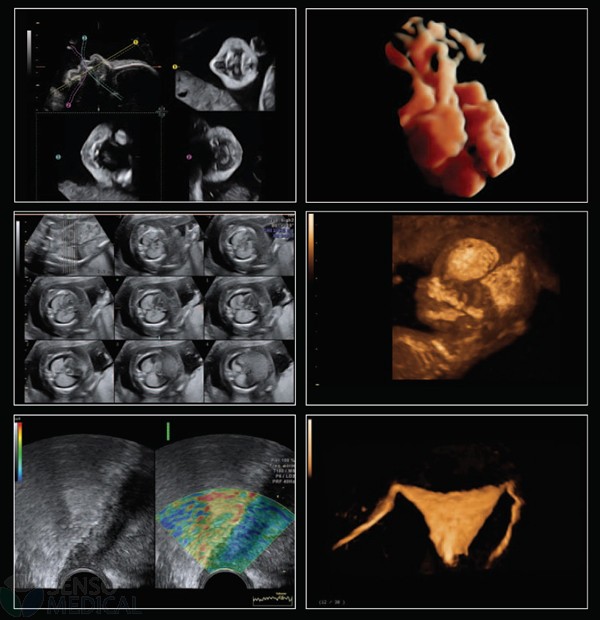

Ultrasonograf GE Voluson E6 wersja oprogramowania BT13 (UISApp 13.0.6.254) 4D HDLive –

rekondycjonowany 2019

Innowacyjna sonda endowaginalna 4D o wysokiej rozdzielczości pomaga odkryć najdrobniejsze szczegóły i pomaga zwiększyć pewność diagnostyczną.

System Voluson E6 to unikalne rozwiązanie w zakresie diagnostyki chorób kobiecych oferujące wysoką jakość obrazowania w trybach 2D i 3D/4D oraz uproszczone procedury usprawniające przepływ pracy i zapewniające najwyższą jakość badań. Więcej szczegółów, mniej wysiłku!

Oprócz najnowocześniejszych opcji obrazowania w usg 2D 3D 4D oraz opcji dopplerowskich posiada także funkcję ELASTOGRAFII.